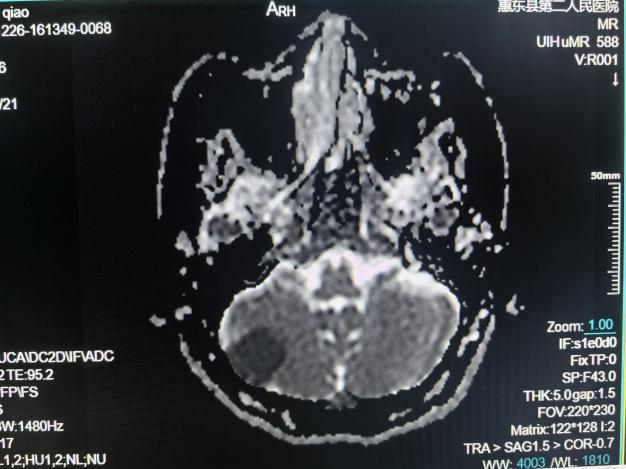

颅脑MRI检查

①先天性颅脑发育异常:包括器官源性畸形和组织源性畸形,MRI可确诊;②脑积水;③脑萎缩;④卒中及脑缺氧:脑梗塞和脑出血等;⑤脑血管疾病:高磁场的MR通过血管成像(MRA)技术显示;⑥颅内肿瘤和囊肿;⑦颅脑外伤;⑧颅内感染和其他炎性病变;⑨脑白质病。

急性脑梗死磁共振成像